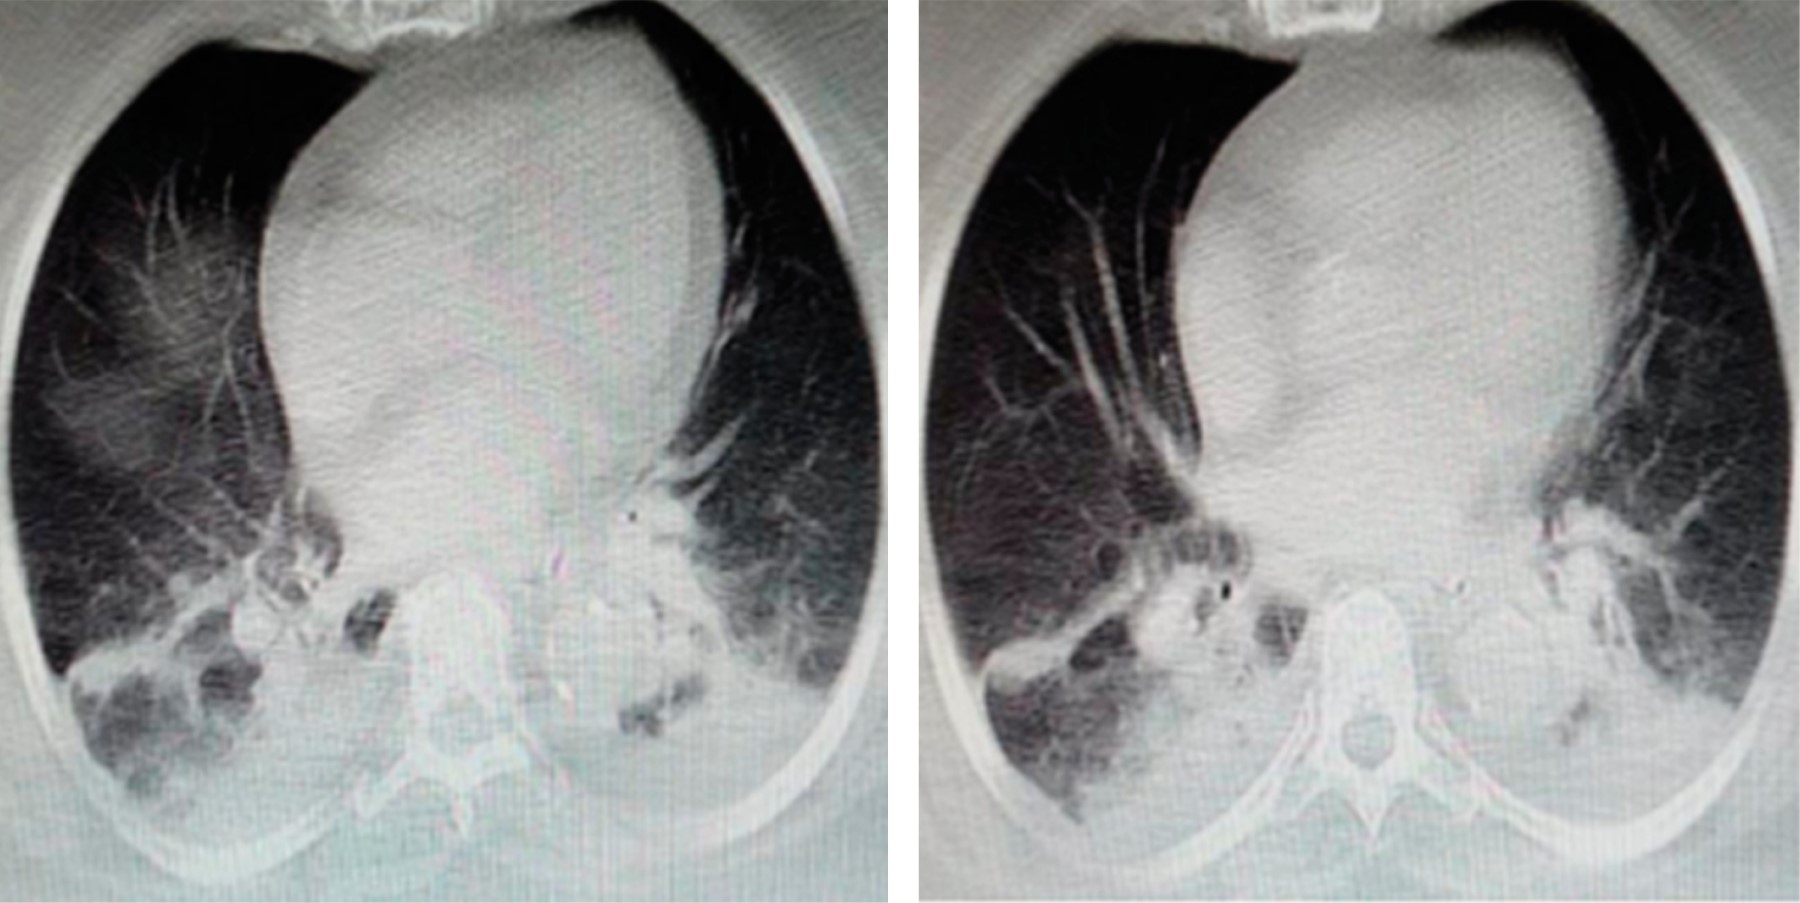

We present the clinical case of a 59-year-old patient with sepsis due to polymicrobial pneumonia with viral isolates conditioning bacterial infection and thrombosis. His chest scannography reported basals collapses with atelectasis and reticular interstitial infiltrates; Evolved with cognitive impairment related to multi-infarction vascular brain disease documented by single-photon emission brain tomography by nuclear medicine due to normal scannographies studies; Given the neurological evolution, extension studies were carried with transthoracic duplex Doppler echocardiogram which was normal, as well as a contrasted study of four neck vessels, electrical rhythm holter and complete metabolic profile also normal. We conducted a review in the literature with a view to providing understanding and evidence of the direct relationship between septic syndromes and viral infections with different states of hypercoagulability, inflammation and apoptosis.

Figure 3